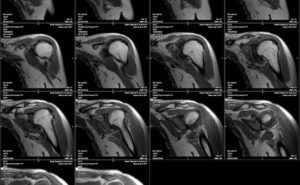

Результатом МР-сканирования являются послойные изображения исследуемой области в трех, взаимноперпендикулярных проекциях. Анализом фото занимается врач-рентгенолог, который фиксирует и описывает любые отклонения структуры сустава от нормы.

Пример снимка МРТ здорового сустава.

На снимках преобладают серые оттенки, интенсивность которых зависит от плотности обследуемых структур. При необходимости на экране монитора создается трехмерное изображение, наиболее информативное при проведении МРТ с контрастным веществом.